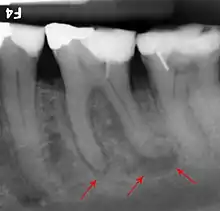

The proximity of the root to the canal can be assessed radiographically and there are several factors which can indicate high risk of nerve damage:[18]

- Darkening of the tooth root where it crosses the canal[18]

- Deviation of the canal[18]

- Narrowing of the roots[18]

- Loss of the lamina dura of the canal[18]

- Juxta apical area: a radiolucency associated with the root of the tooth which is not caused by periapical infection[18]